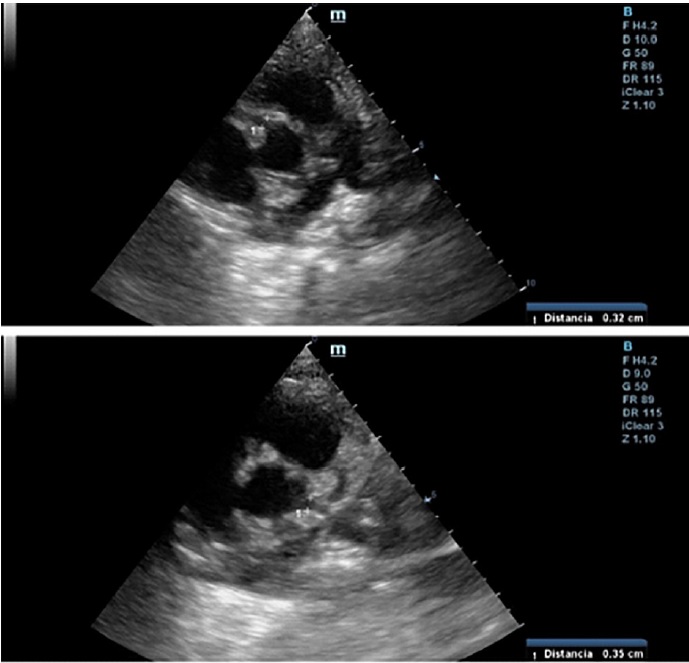

We present the case of a 30-year-old male patient with history of non-atherosclerotic dilated ischemicnecrotic cardiomyopathy, with reduced left ventricular ejection fraction (LVEF) (35%) and ventricular aneurysm (Figure 1), as a result of extrinsic iatrogenic lesion following anterior descending artery suture due to gunshot wound and urgent surgery. He subsequently underwent various hospitalizations for recurrent sustained monomorphic ventricular tachycardia (SMVT) (Figure 2a), leading to implantable cardioverter defibrillator (ICD) placement and substrate ablation, with favorable outcome.

Fig. 1 T2 sequence magnetic resonance coronal section showing left ventricular dilation, presence of apical aneurysmatic sac, myocardial thinning and low-intensity signal.